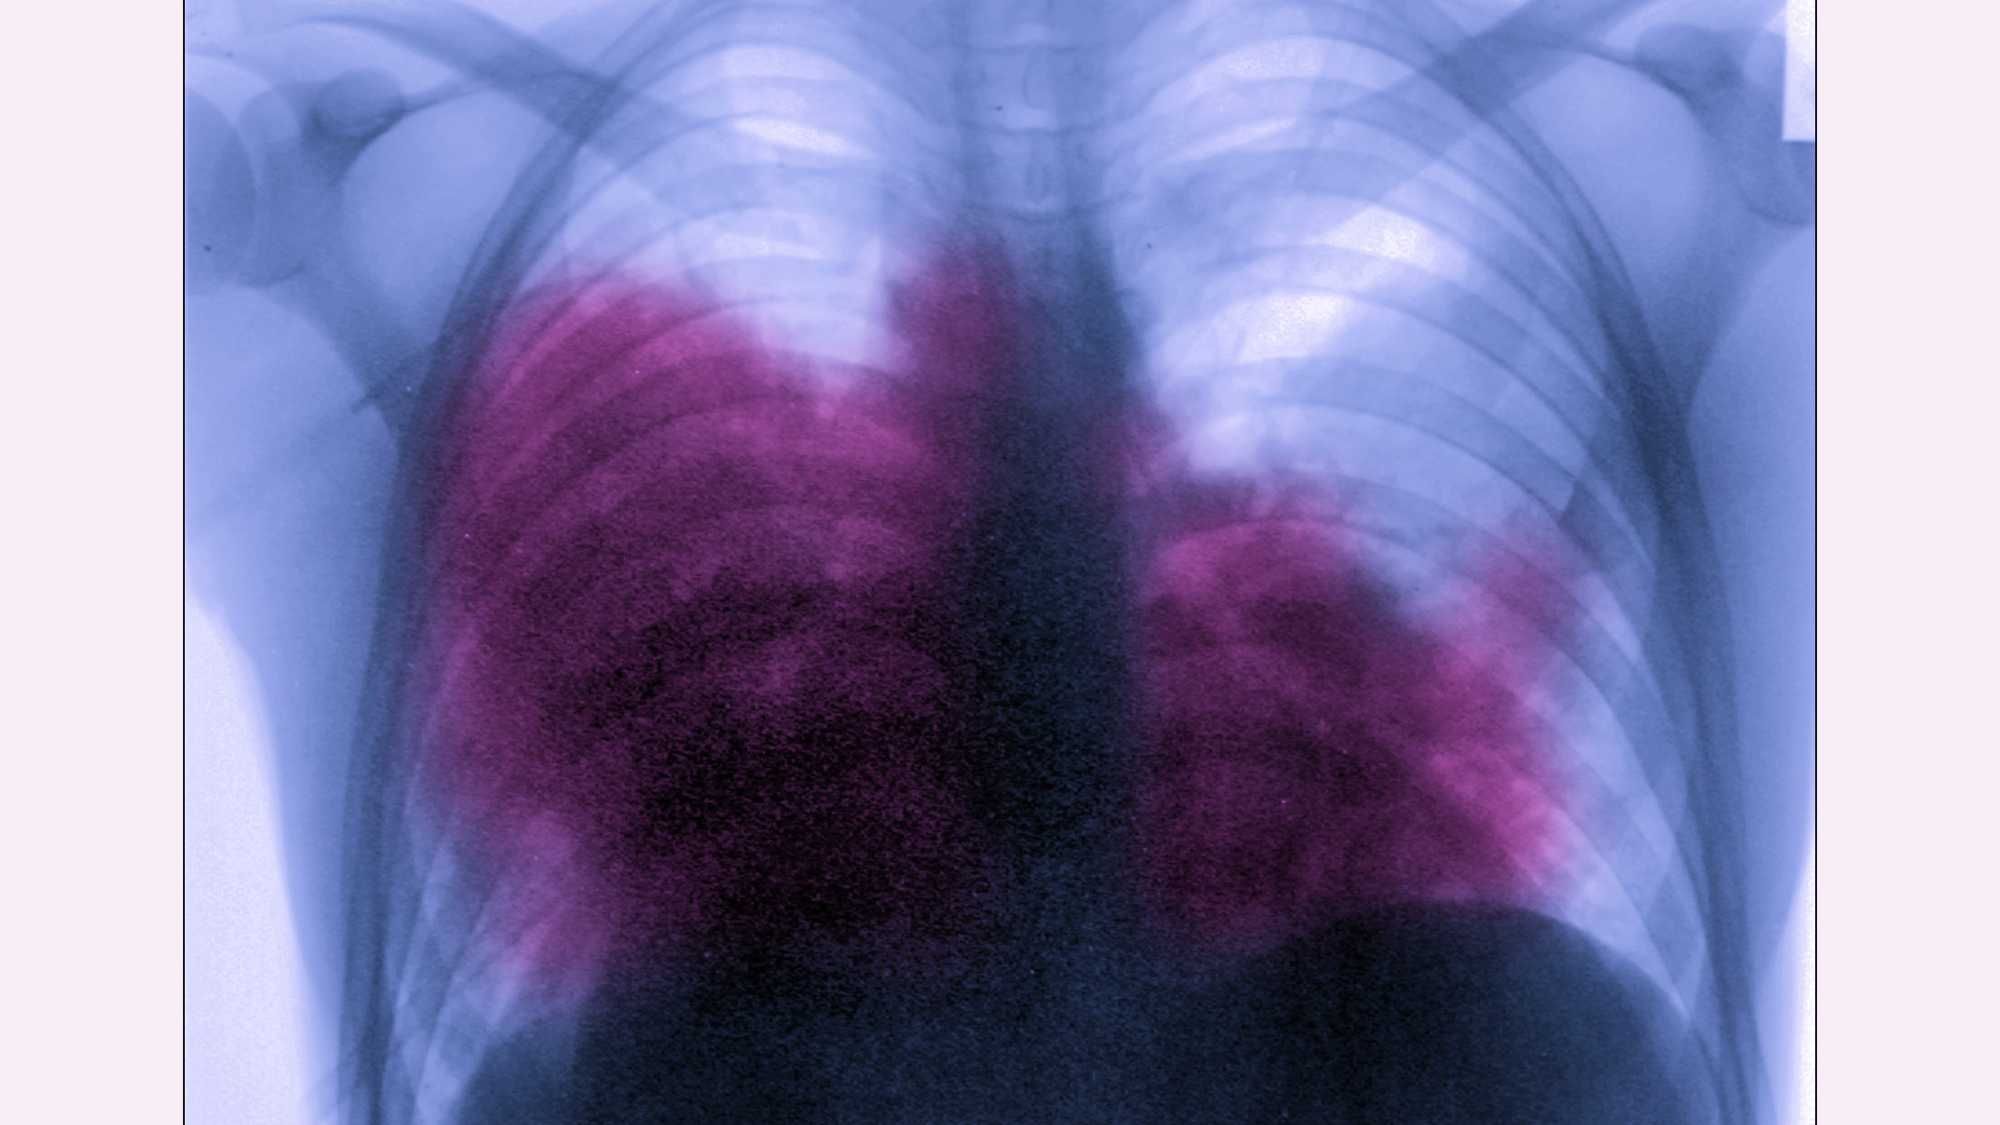

People contract Legionnaires' disease by breathing in water vapor contaminated with Legionella bacteria which grows in warm water. It's not contagious and can be treated with antibiotics if caught early.

Legionnaires' disease is characterized by Flu-like symptoms. Those above the age of 50, cigarette smokers and people with chronic lung disease are at higher risk.